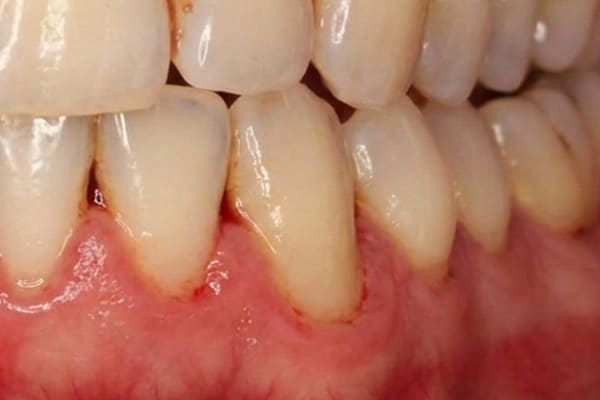

軽度歯周炎 危険度★★

軽度の歯周炎は歯茎が少し赤みを帯び腫れた状態になります。

軽度歯周炎の場合の目安は歯周ポケットが3~4mm程度と言われています。

この段階での治療法は、プラークや歯垢をスケーリングなどで取り除き、正しいブラッシングを毎日することです。